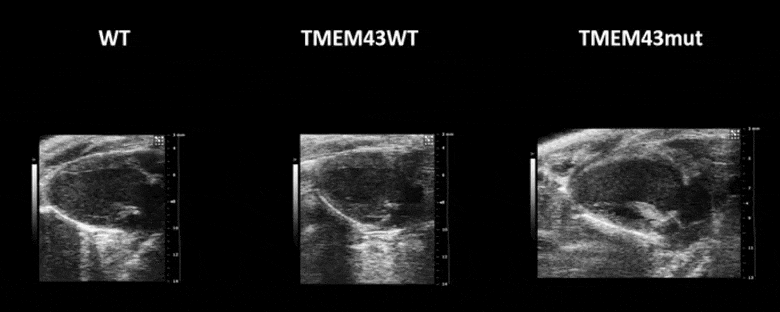

Figure 1. Mutation p.S358L in TMEM43 induces biventricular dysfunction and accumulation of fibrofatty tissue in the myocardium. WT, wild type mice; TMEM43wt, mice overexpressing the wild type version of human TMEM43 in cardiomyocytes; TMEM43mut, mice expressing the mutant version of human TMEM43 in cardiomyocytes. Full paper here.

Video 1. Expression of TMEM43 with the p.S358L mutation results in severe cardiac contraction. The video shows echocardiographic images of the left ventricle in the longitudinal axis (please note the resolution of the video has been reduced). WT, wild type mice; TMEM43wt, mice overexpressing the wild type version of human TMEM43 in cardiomyocytes; TMEM43mut, mice expressing the mutant version of human TMEM43 in cardiomyocytes. Full paper here.